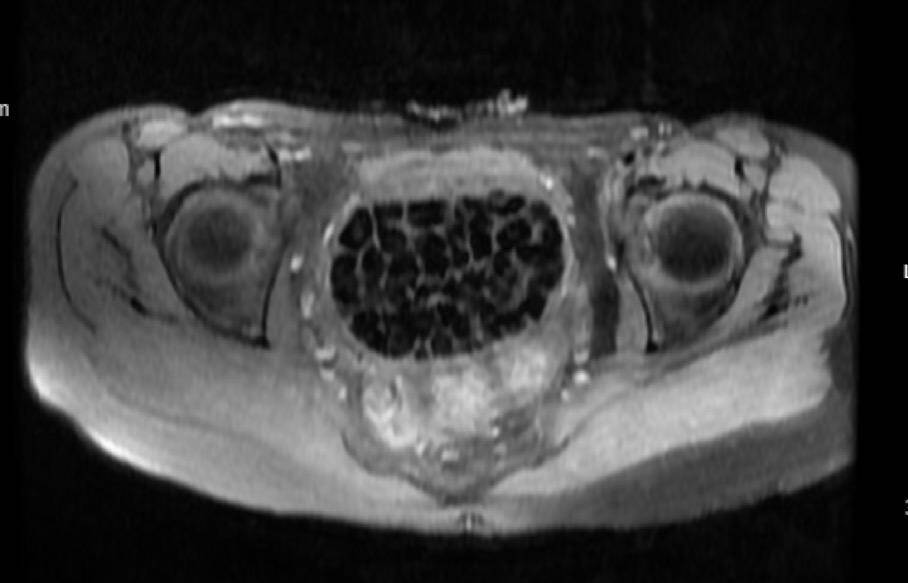

Genç kızın ameliyat işlemleri başlatılırken 11 Eylül’deki operasyon sırasında doktorlar da şaşkınlık yaşadı. Öztürk’ün vücudundan 287 adet çeşitli ölçülerde taş çıkarılırken üroloji ve jinekolojik onkoloji ekibi operasyonu başarıyla tamamladı. Taşların sayısını duyan genç kız ve ailesi şok olurken operasyonun ardından karın ağrıları dinen Öztürk, rahat bir nefes aldı. Tedavisi sonrası taburcu edilen genç kız yaşadıklarını anlatırken, operasyonu gerçekleştiren Üroloji Uzmanı Doç. Dr. Erkan Erkan ile Jinekolojik Onkoloji Uzmanı Op. Dr. Emin Erhan Dönmez de nadir olduğunu ifade ettikleri vakaları hakkında bilgi verdi, önemli uyarılarda bulundu. Öte yandan, genç kızın vücudundaki 287 taşın tetkiklerdeki görüntüsü dikkat çekerken taşlar üzerine de incelemeler yapılacak.

Hastasının durumuna yönelik konuşan Üroloji Uzmanı Doç. Dr. Erkan Erkan, "Hastamızın 2004 yılında doğduğunu ardından doğar doğmaz ekstrofi vezika dediğimiz 50 binde bir görülen bir anomaliden dolayı art arda ameliyatlar geçirdiğini öğrendik. 10 yaşında yine bir ameliyat geçirmişti, gerekli görüntüleme ve tetkiklerimizi yaptırdık. Normalde mesanesinin olması gereken yerin hemen arka kısmında taşlarla dolu bir kese olduğunu gördük, bunun üzerine ek görüntülemeler; MR çektirdik. Hastamız çelişkili açıklamalar almıştı, kendi radyolojik kliniğimiz ve edindiğimiz konsültasyonlarda taşların mesanede değil vajinal boşlukta oluştuğunu düşündük, bir planlama yaptık. Kadın doğum hocamızın da çabasıyla taşları tamamen temizledik ardından ileride normal bir hayat sürmesi bakımından oraya plastik cerrahi yaptık. 287 adet taş çıkardık, pratikte gerçekten görünce çok şaşırdık çünkü bu aynı zamanda literatürde çok nadir görülen bir olay. Biz ameliyata hazırlanırken de teorik olarak biraz araştırdık. Literatürde gördüğümüz kadarıyla buna benzer bu tanıma uyan bir vaka vardı. Literatürde sanırım yayınlanmış 2’nci vaka olacak. Farkındalık çok önemli, bilinçli bir hastamız vardı. Doğumsal anomaliyle doğan çocuklarımızda ileride bunlara bağlı bazı sıkıntılar çıkabileceğinin öngörülmesi lazım. İlgili tedavilerini alsalar bile düzenli takiplere gelmeleri gerekiyor. İleride eğer dikkat etmezse ki zannetmiyorum, tekrarlayabilir. Bu rahatsızlık ekstrofi vezikal epispadias durumu çok nadir bir durum" dedi.

Genç kızın uzun süredir devam eden karın ağrısı olduğunu söyleyerek sözlerine başlayan Jinekolojik Onkoloji Uzmanı Op. Dr. Emin Erhan Dönmez, "Mesane taşları olduğu düşünülerek daha büyük bir hastaneye refere edilmiş. Aramızda mini bir konsey yaparak muayene ettik. Vajen bir hazne görevi görerek orada durağan bir idrar, uzun süre beklediği için idrar içindeki minerallerde çökerek taşlar oluşmuş. Mesanedeki idrarın vajene akmış olabileceği ve vajende göllenen idrar nedeniyle taşların burada oluşacağını düşündük, ameliyatımızı planladık. Ameliyata tanı amaçlı girmiştik, sistoskopi (Mesane gibi idrar yollarını kapsayan kısımlardaki rahatsızlıkların teşhis ve tedavisinde kullanılan endoskopik bir yöntem) dediğimiz ameliyatı Erkan Hocam ile birlikte gerçekleştirdik. Önce mesaneyi bir görüntüledik, mesane tabanına yaklaşık 2-3 cm’lik bir alandan vajene fistülize olduğunu gördük. Mesaneden vajene geçtiğimiz esnada tüm vajenin taşlarla dolu olduğunu gördük. Tanı amacıyla girdiğimiz ameliyatta her şey de olağan gittiği için tedaviye geçtik. Taşların çıkabileceği kadar bir genişlik sağladık. Daha sonra yaklaşık en büyüğü 2,5 cm boyutlarında olan, irili ufaklı 287 tane taşı ameliyat esnasında çıkarmış olduk. Taşların tekrarlamaması için idrarın göllenmemesi, en azından dışarıya rahatça boşalabilmesi için vajinal rekonstrüksiyonu sağladık. Ameliyatta da herhangi bir problem yaşamadık. Literatürü Erkan Hocam ile birlikte değerlendirmiştik. Primer olarak vajende birikmiş olan bu kadar çok sayıda taşla ilgili bir makale görmedik, rastlamadık" dedi.